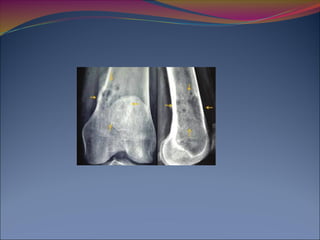

14 Rayos X:

Cráneo (AP y Lat)

Columna Cervical (AP y Lat)

Columna Torácica (AP y Lat)

Columna Lumbar (AP y Lat)

Fémur (AP y Lat)

Húmero (AP y Lat)

Tórax (PA)

Pelvis (PA)

80% de los pacientes tienen alteraciones en las Rx

Blood. 2011 May 5;117(18):4701-5.

14 Rayos X: Cráneo(AP y Lat) Columna Cervical (AP y Lat) Columna Torácica (AP y Lat) Columna Lumbar (AP y Lat) Fémur (AP y Lat) Húmero (AP y Lat) Tórax (PA) Pelvis (PA) 80% de los pacientes tienen alteraciones en las Rx Blood. 2011 May 5;117(18):4701-5.